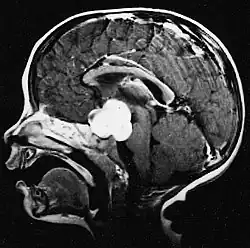

Pilocytic astrocytoma (and its variant pilomyxoid astrocytoma) is a brain tumor that occurs most commonly in children and young adults (in the first 20 years of life). They usually arise in the cerebellum, near the brainstem, in the hypothalamic region, or the optic chiasm, but they may occur in any area where astrocytes are present, including the cerebral hemispheres and the spinal cord. These tumors are usually slow growing and benign, corresponding to WHO malignancy grade 1.[1]

Usually – depending on the interview of the patient and after a clinical exam which includes a neurological exam and an ophthalmological exam – a CT scan and/or an MRI scan will be performed to confirm the presence of a tumor. They are usually easily distinguishable from normal brain structures using these imaging techniques. A special dye may be injected into a vein before these scans to provide contrast and make tumors easier to identify. Pilocytic astrocytomas are typically clearly visible on such scans, but it is often difficult to say based on imaging alone what type of tumor is present.

Pilocytic astrocytomas are often cystic tumors, and, if solid, tend to be well-circumscribed.